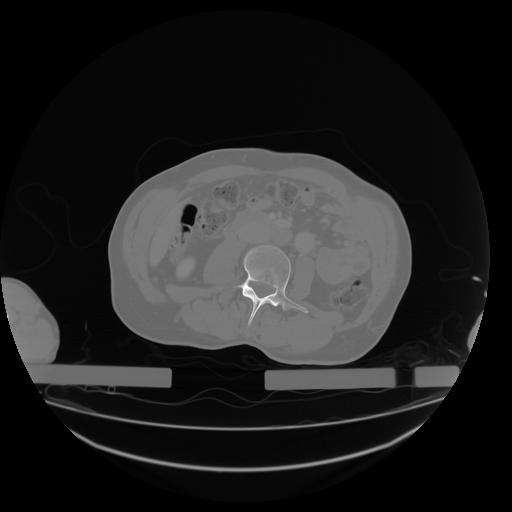

27 CUERPO,CE,Axial,3.0,CUERPO,,